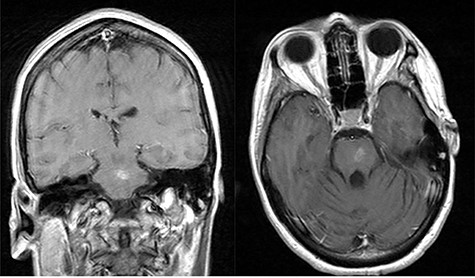

Post-op axial, coronal and sagittal T1 post-contrast MRIs demonstrating decrease size of rim enhancing pontine abscess.

Three days after initial presentation, she underwent sub-occipital craniotomy for microsurgical abscess drainage. Initial consideration was given to a stereotactic procedure; however, an open approach was ultimately chosen due to surgeon preference. Intraoperative neuro navigation was used with subsequent creation of a posterior fossa craniotomy. This approach was chosen over a retrosigmoid approach, given the midline nature of the lesion. The dura was opened over the right cerebral hemisphere and tonsil at which time pus was expressed and was cultured immediately at the operative site. We were unable to dissect the roof of the fourth ventricle secondary to a large volume of pus and instead retracted the bilateral tonsils and resected a small amount of the inferior vermis. Facial colliculus was localized and an incision was made in the midline medial raphae. Incision into the brainstem did not express any purulence, so the wound was copiously irrigated and subsequently closed without advancing further into the brainstem. Cultures from the abscess grew step intermedius and antibiotics were narrowed accordingly. Over the next several weeks, the patient remained afebrile with no leukocytosis, but there was concern for persistent infection due to lack of clinical improvement. Repeat MRI demonstrated enlargement of the residual abscess (Fig. 2a–c), and she was taken back to the operating room for repeat abscess drainage via the same sub-occipital craniotomy incision. During this procedure, the roof of the fourth ventricle was visualized and dissected through before localization of the vagal trigone. Midline raphae was once again opened and intraoperative MRI navigation confirmed the locations of the abscess. Microscopic dissection was performed in the midline between facial colliculi, and spinal needle was passed into the opening with subsequent aspiration of 9-ml purulent fluid, re-aspiration attempt and closure. Repeat gram stain and culture failed to reveal any organisms.